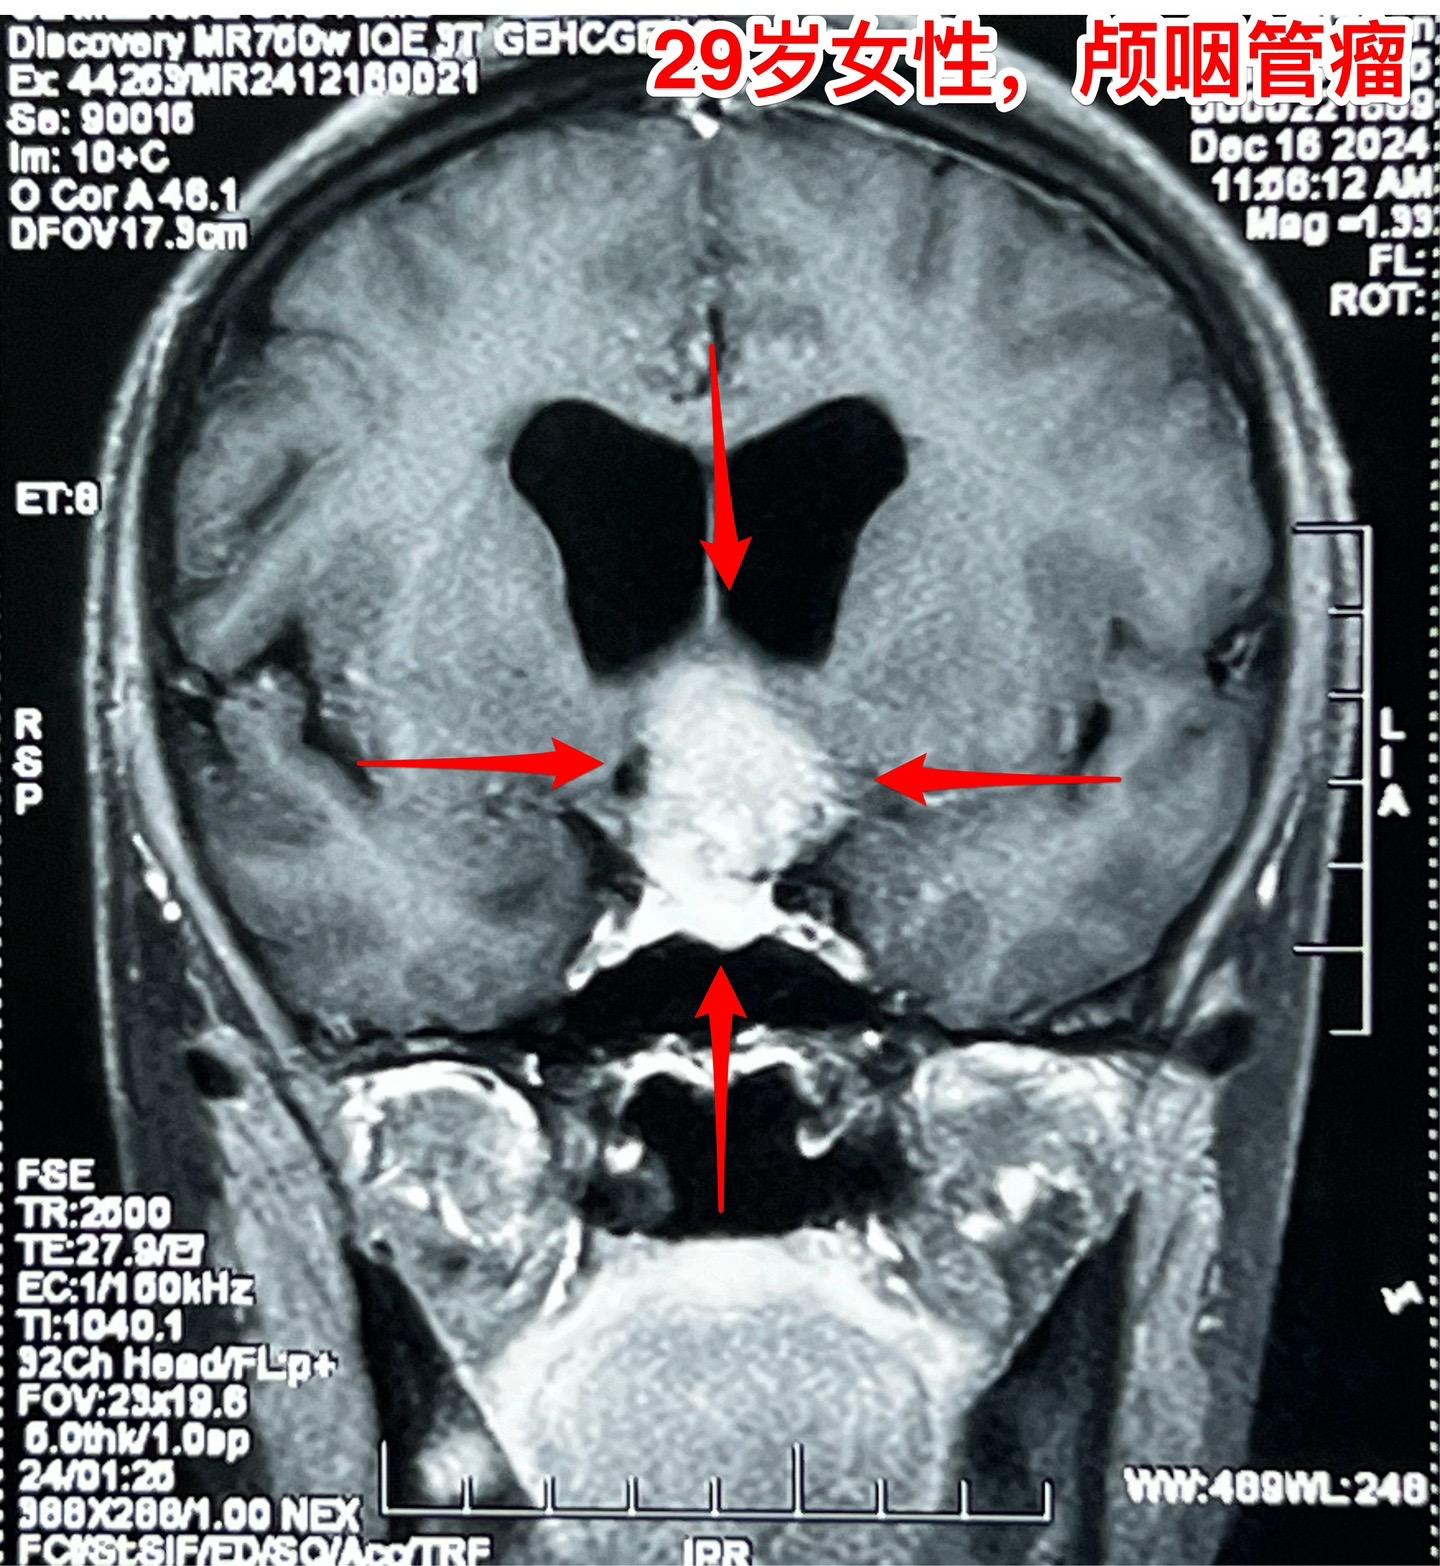

大理市女教师患颅咽管瘤。29岁大理市女老师,因头晕,内分泌功能障碍到医院行脑部CT及磁共振检查,发现颅咽管瘤。CT显示肿瘤有钙化,是典型的造釉细胞性颅咽管瘤。 患者家人系医务工作者。发现颅咽管瘤后即来北京就医。到我院检查视力视野,有视野缺损。 今日在我科作了颅咽管瘤切除手术,手术后5小时病人即清醒了。肿瘤完全切除,垂体柄结构完整,漏斗保留约三分之一。